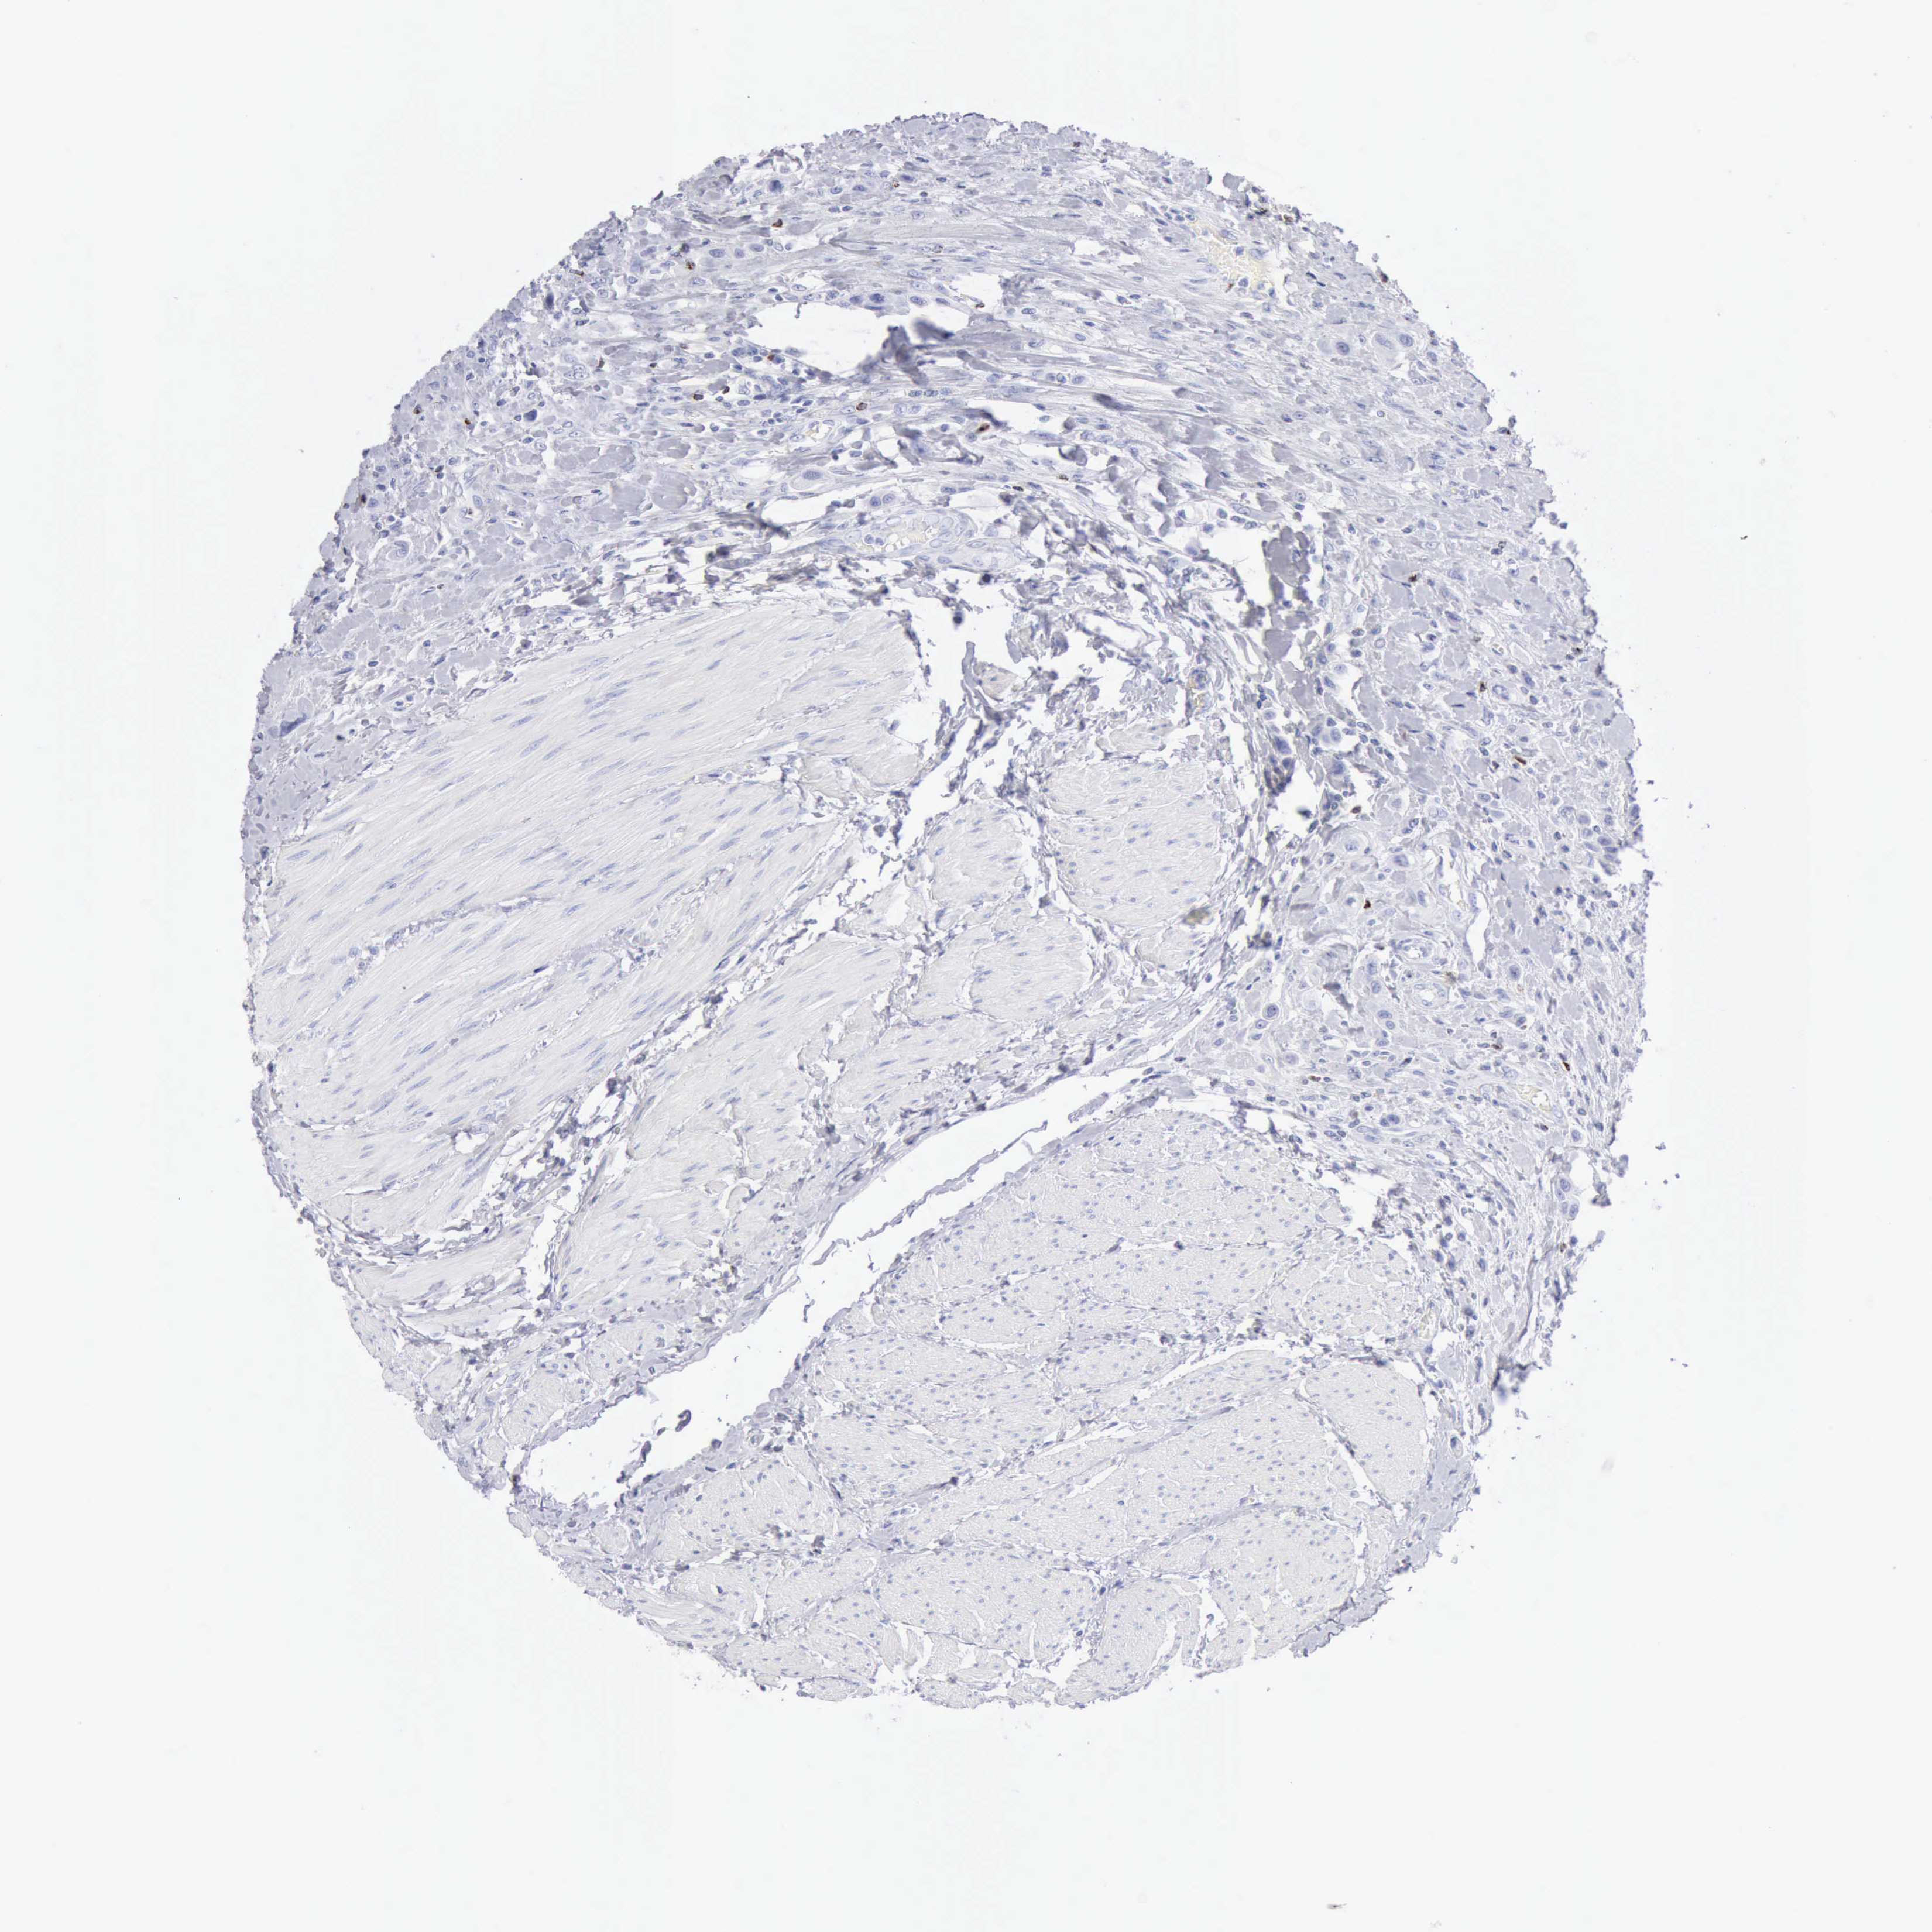

UROTHELIAL CANCER - Protein expressioni

A mouse-over function shows sample information and annotation data. Click on an image to view it in a full screen mode. Samples can be filtered based on level of antibody staining by selecting one or several of the following categories: high, medium, low and not detected. The assay and annotation is described here.

Note that samples used for immunohistochemistry by the Human Protein Atlas do not correspond to samples in the TCGA dataset.

Antibody stainingi

Antibody staining in the annotated cell types in the current human tissue is reported as not detected, low, medium, or high, based on conventional immunohistochemistry profiling in selected tissues. This score is based on the combination of the staining intensity and fraction of stained cells.

Each image is clickable and will lead to virtual microscopy that enables deeper exploration of all samples and also displays staining intensity scores, fraction scores and subcellular localization as well as patient and tissue information for each sample.

Antibody HPA003418

Antibody CAB000376

Urothelial carcinoma, High grade

Urothelial carcinoma, Low grade